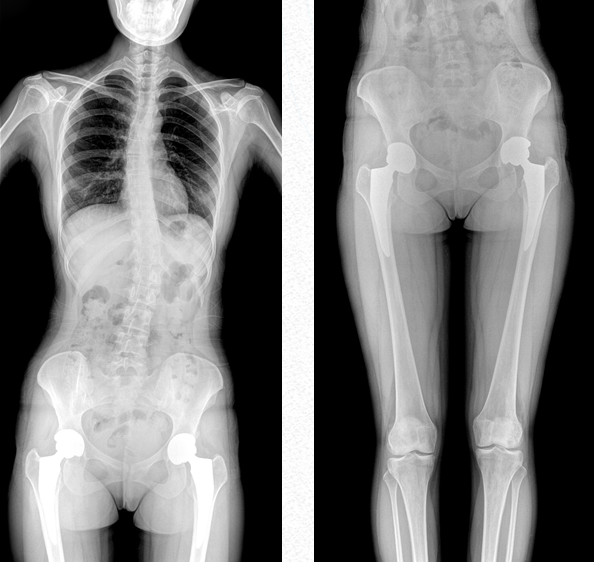

雙下肢成像

用于創傷弓|起的四肢骨折,進行較長髓內釘術前診斷、術后復診的大視野攝影。

關節運動成像

雙下肢關節運動動態攝影以及數字化動態造影等大視野臨床應用。

PLX8600大視野動態平板DR可攝影、可透視、可造影,臨床適用范圍廣泛,滿足臨床拍攝需求。與市面常規多張攝影再軟件拼接的DR相比,PLX8600大視野動態平板DR解決了拼接圖像存在密度不均勻,拼接處圖像配準和放大效應等問題,一體式的機架,擺位簡單快捷 ,具有畸變率低、測量精度高、圖像質量好、無拼接痕跡等優點。這款DR不僅融合了市面上17*17英寸動態DR的功能,除此之外它獨具特色的17*34英寸超大動態視野范圍,給臨床應用帶來較高價值,減輕醫院設備投入成本,獲得更大收益。